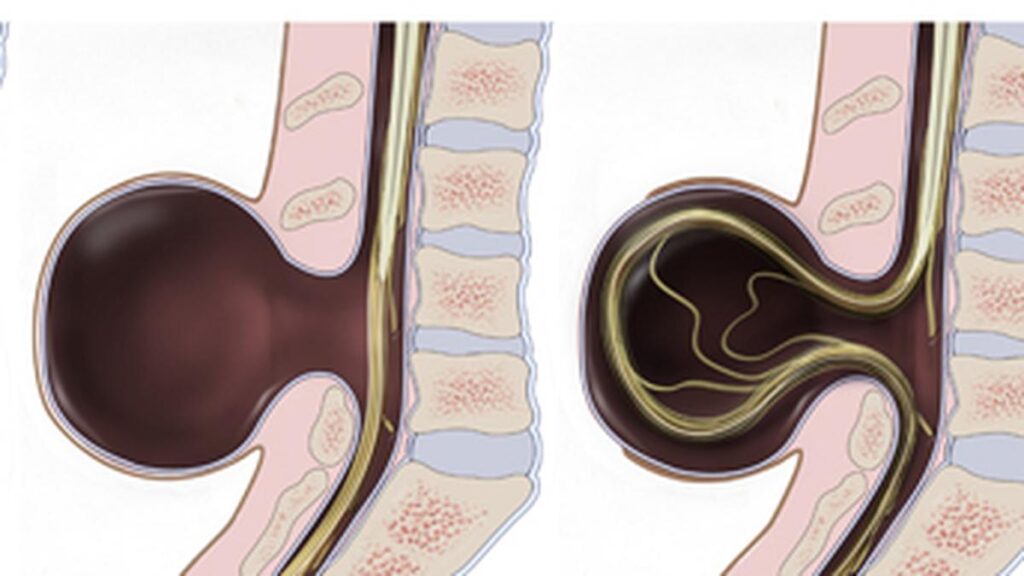

There are three main types of spina bifida. The most serious form of the condition is myelomeningocele or open spina bifida. In this type, part of the spinal cord and nerves are exposed through a sac at the opening of the gap in the spine. The second type, meningocele, is a less common type of spina bifida that occurs when the meninges, or the protective membranes around the spinal cord, push out through the opening in a fluid-filled sac. Usually, in this type, the spinal cord has developed normally and the nerves are not affected. The third type of the condition is known as spina bifida occulta or ‘hidden’ spina bifida. This is mildest form of the condition in which one or more of the vertebrae not forming properly, resulting in a small gap. It usually does not cause any symptoms and many people with the condition are not aware that they have it.

Surgery is one treatment option available. Surgery may be done before birth, while the baby is still in the womb, or just after birth, for severe cases of myelomeningocele. This is done in order to close the gap in the spine and protect the developing spinal cord from being exposed. Surgery while the baby is in the womb has risks for both mother and baby, but some researchers believe it can lead to better outcomes for the baby and decrease disability. Babies with hydrocephalus may need a surgery to help drain the fluid out. Some may also require surgery for tethered spinal cords — a condition, where the spinal cord, instead of floating freely, is attached to the spinal canal.